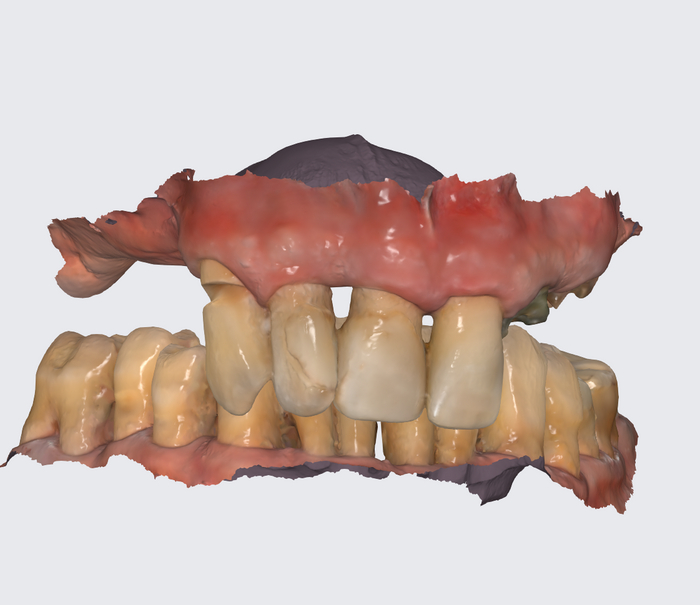

Вариант 1 - большие зубы, но без розовой десны.

Протез FP2

Вариант 2 - зубы нормального размера, но десна розовая в наличии.

Протез FP3

Что выбираете?

Пациент сам выбрал:

цвет зубов А4;

протез с розовой десной.

Плохо, что ли? Хорошо.

Такая работа стоит +/- 300 000 рублей сейчас (протез временный условно-съёмный). Имплантаты Neodent.

"всё на 4-х", верхняя челюсть, временный протез адаптационный